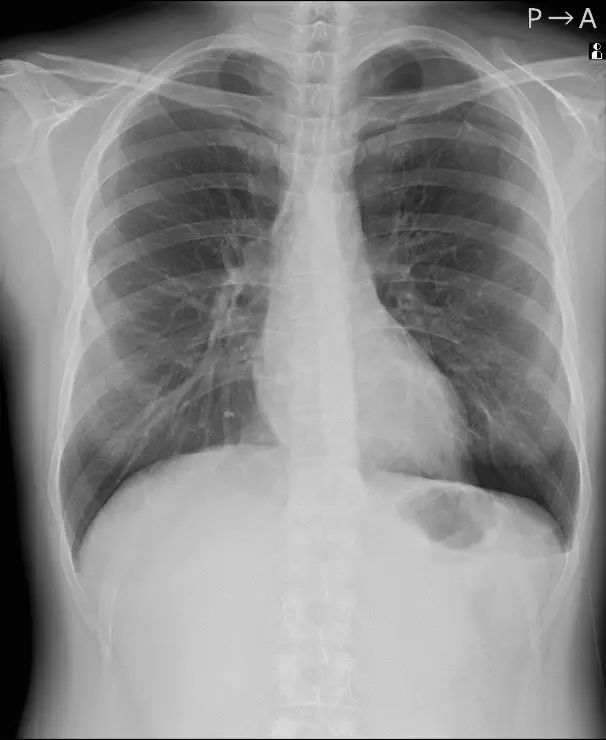

人のレントゲン写真 オリジナル画像

オリジナル画像